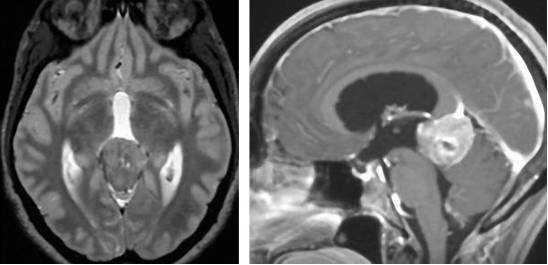

图7. 室管膜下瘤并不会显著增强,在T2相上与邻近白质和灰质相比,表现为高信号。而在T1相上,则表现为等或低信号。上图中病灶位于四脑室底。